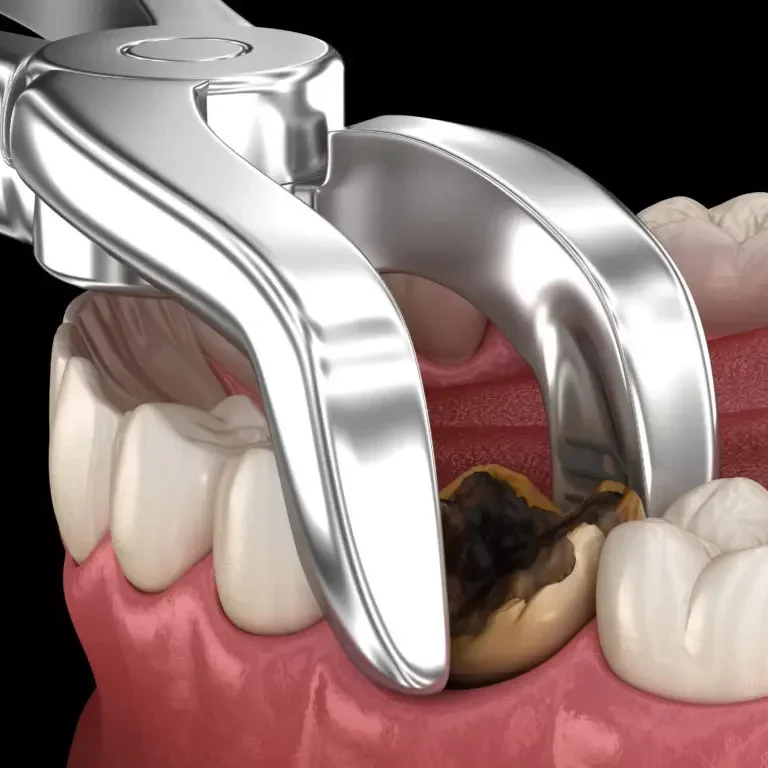

Extracción dental

Proceso que consiste en remover un diente de su alveolo del hueso maxilar o mandibular.